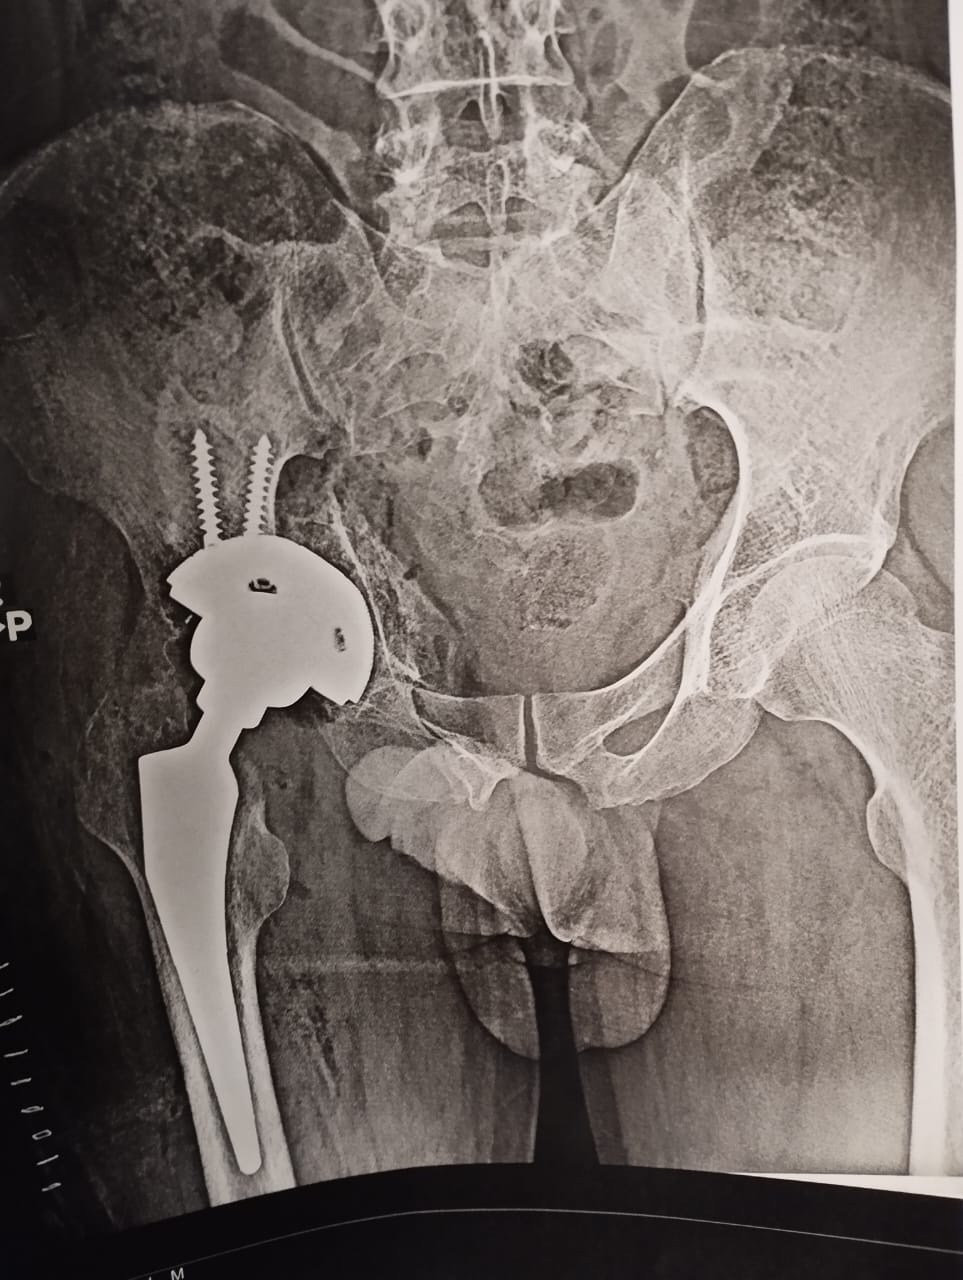

من جانبه قال الدكتور مجدي القاضي عميد كلية الطب بجامعة سوهاج انه تم تقييم الحالة الصحية لأحد المرضي الأشقاء من أهالى غزة، ويبلغ من العمر 41 عاما ويعانى من خلع بمفصل الحوض منذ ٦ شهور، وعلى الفور تم إجراء العملية الجراحية للمريض وتركيب مفصل حوض كامل، مضيفًا أن ادارة المستشفي تولي اهتمام كبير ورعاية مستمرة لجميع مصابي غزة منذ ان وطأت أقدامهم المستشفي الجامعي، وذلك تنفيذًا لتوجيهات الدكتور حسان النعماني رئيس الجامعة واهتمامه البالغ بمتابعته المستمرة لمستوي التحسن لحالتهم الصحية.

تغيير كامل لمفصل الفخذ من ابناء غزه فى مستشفى سوهاج الجامعى

وقال الدكتور عبدالرحمن الشيخ رئيس قسم العظام بمستشفى سوهاج الجامعى انه تم استقبال المريض بقسم العظام وإجراء الفحوصات والتحاليل المخبرية والأشعات اللازمة وعلي الفور تم تشكيل الفريق الطبي المعالج الذي اجري العملية الجراحية ببراعة كبيرة، حيث بلغت تكلفة المفصل ٨٥ الف جنيه كتبرع من قسم العظام، موضحًا ان الفريق الطبي تكون من الدكتور ياسر عثمان استاذ جراحة العظام، الدكتور حسام حسنى والدكتور محمد شحاتة وعدد من الاطباء بالقسم وشكر خاص لفريق الهيئة التمريضية علي مابذلوه لإنجاز هذا العمل الانساني الكبير.